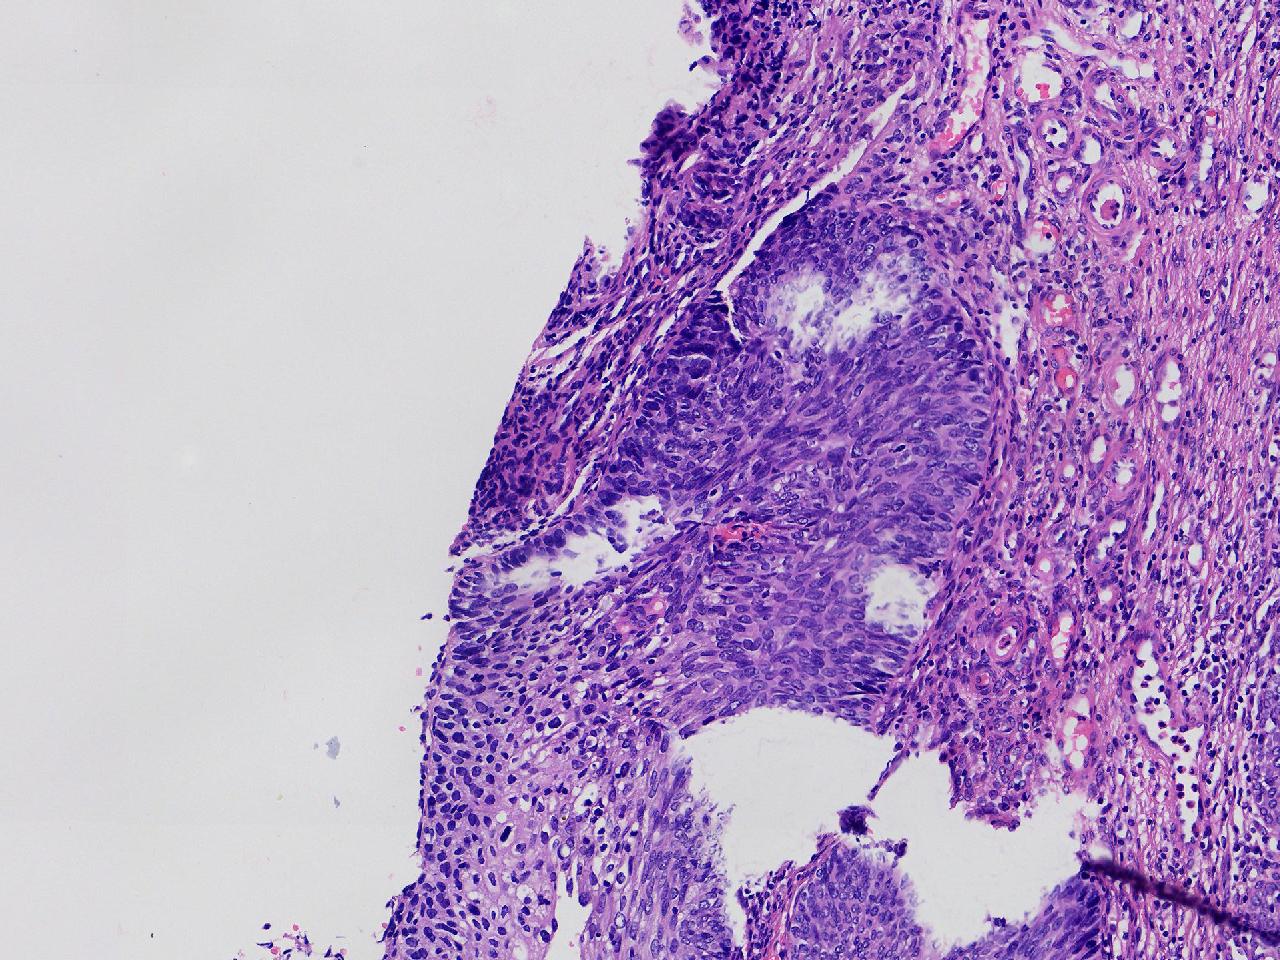

CIN1级? CIN2级?

女,49岁,宫颈11点活检,HPV:16+ 42+

宫颈11点活检。

灰白色不整形软组织1块。

图1

2级

2级,累腺。